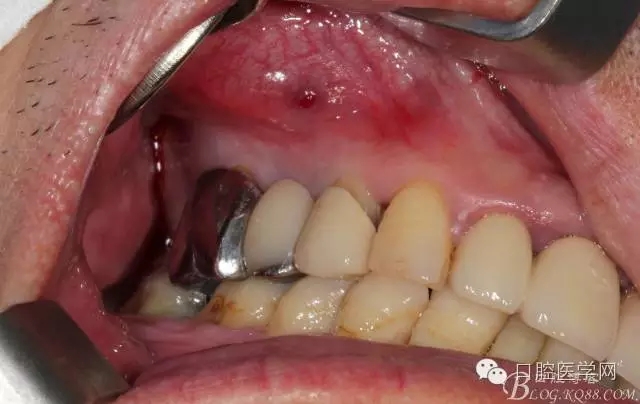

牙周治療以后過了段時間我們開始拔牙種牙,上圖是牙周治療以后開始種牙的口內(nèi)照片,效果還是有的。

拔牙以后 拔牙窩少許肉芽 發(fā)現(xiàn)13遠中還是有些肉芽的

簡單清理以后 (一般這種情況我是不太翻瓣的 )這個患者我在清理13遠中時候我發(fā)現(xiàn)有些肉芽而且超過了我的預期的量,我開始不太淡定了 。 我在想牙周科同事是不是知道我要拔牙,沒有在14 16 牙位用洪荒之力刮治啊。結(jié)果我翻瓣一點點去檢驗了下牙周科刮治的效果,那么結(jié)果是非常好,沒啥太多的肉芽,不翻瓣完全可以刮干凈,看來我得信任我的同事啊,牙周科非常給力。13牙位遠中的肉芽估計的確不好刮掉,所以留給我刮了吧。